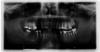

AlekseyKur Опубликовано 3 февраля, 2010 Поделиться Опубликовано 3 февраля, 2010 (изменено) Уважаемые доктора. Вы мне уже один раз очень помогли советом. Большое Вам, человеческое спасибо.В настоящее время я начинаю долгий процесс протезирования. Поделитесь пожалуйста Вашим мнением, какие варианты протезирования нме больше подходят. Снимок тут: т в прикреплённом файле.http://s003.radikal.ru/i204/1002/32/5317a64e835bt.jpg Изменено 3 февраля, 2010 пользователем AlekseyKur Ссылка на комментарий

Bier Опубликовано 4 февраля, 2010 Поделиться Опубликовано 4 февраля, 2010 два имплантата справа наверху и 2 справа внизу, все мертвые зубы под вкладки и коронки. Ссылка на комментарий

AlekseyKur Опубликовано 4 февраля, 2010 Автор Поделиться Опубликовано 4 февраля, 2010 (изменено) два имплантата справа наверху и 2 справа внизу, все мертвые зубы под вкладки и коронки.Ух ты. Спасибо за мнение. Всё таки, видимо, хорошие доктора думают примерно одинаково.Только вернулся с консультации ортопеда. В принципе, те же самые рекомендации. Мы правда около часа это всё оговаривали, но план примерно такой.1) Профессиональная чистка2) Лечение и перелечивание всего чего нужно. (куча всего, всё не запомнил)3) Вкладки+коронки и мосты (вариант 1) или там же гда указали Вы импланты (Вариант 2 - вот тут (импланты или мосты) уже моё решение, так как разница в цене всё таки существенна.)Доктор рекомендовал вкладки из Кобальт Хромового сплава и коронки на его же основе. Рассматривалось и золото в сплаве как вариант. (думаю, так как цена вкладки получается намного выше) Изменено 4 февраля, 2010 пользователем AlekseyKur Ссылка на комментарий